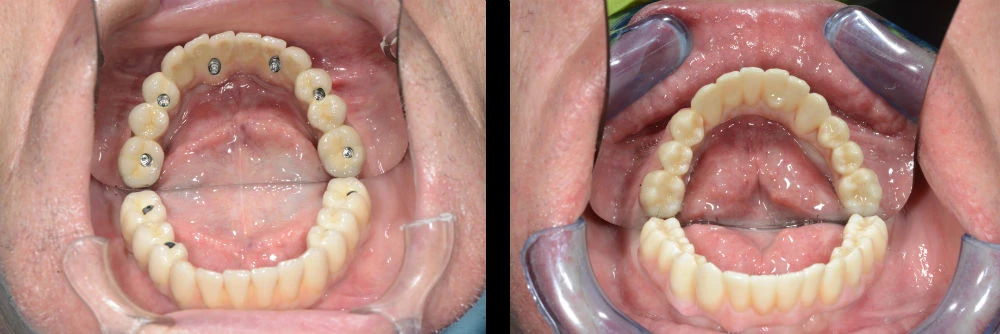

Завършеното лечение и при двете ситуации се осъществява с неподвижен мост от 12 зъба върху 4 импланта – CAD/CAM, циркониев, винтово закрепен, при нужда сваляем без да се унищожава.

Пакетната цена включва всички необходими хирургични интервенции за поставянето на имплантите; изработването на временната, винтово закрепена конструкция от 10 зъба, както и изработването и поставянето на постоянната циркониева, винтово закрепена мостова конструкция от 12 зъба.

И двете конструкции (временна и постоянна) са дигитално проектирани от денталните лекари в „Дента Консулт“, изработени са с CAD/CAM технология в нашата собствена зъботехническа лаборатория, което осигурява най-висок контрол върху качеството и използваните материали за завършване на протетичния етап от Вашето лечение.

Открити отвори 6 импланта Закрити отвори 6 импланта